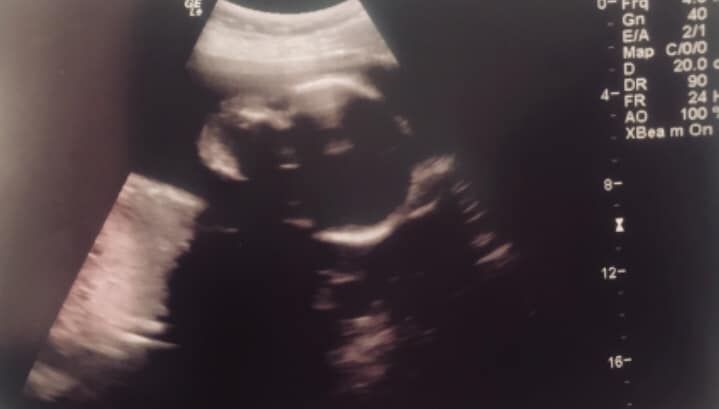

Tara was emotionless when she came to a PreBorn! Pregnancy Center in Mississippi and heard her baby’s heartbeat for the first time. But her mother was extremely thankful. She and Tara’s father decided to parent the baby themselves and thanked the center for giving them the opportunity to see their grandson and hear his heartbeat. Today, they are raising a healthy and happy baby boy!